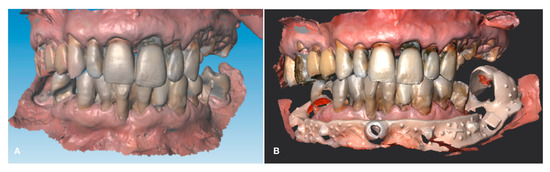

During the intraoral examination, multiple failing teeth were noted in both the maxillary and mandibular arches (Figure 2).

Figure 2. Intraoral frontal view of the patient’s dentition in occlusion.